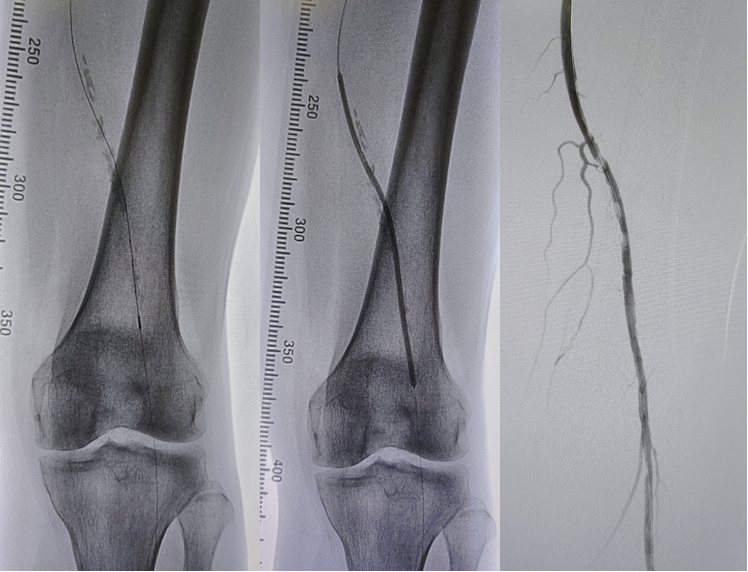

病例2(股腘动脉长段闭塞):

另一例长段闭塞病变,IVUS证实导丝真腔通过后,指导术者选择了合适尺寸的Rotarex导管进行减容,联合普通球囊(POBA)预扩及DCB治疗,获得了满意的管腔,避免了支架植入。

图:导丝通过后3mm球囊预扩

图:多处假腔通过,遂5mm球囊预扩

图:一期支架植入